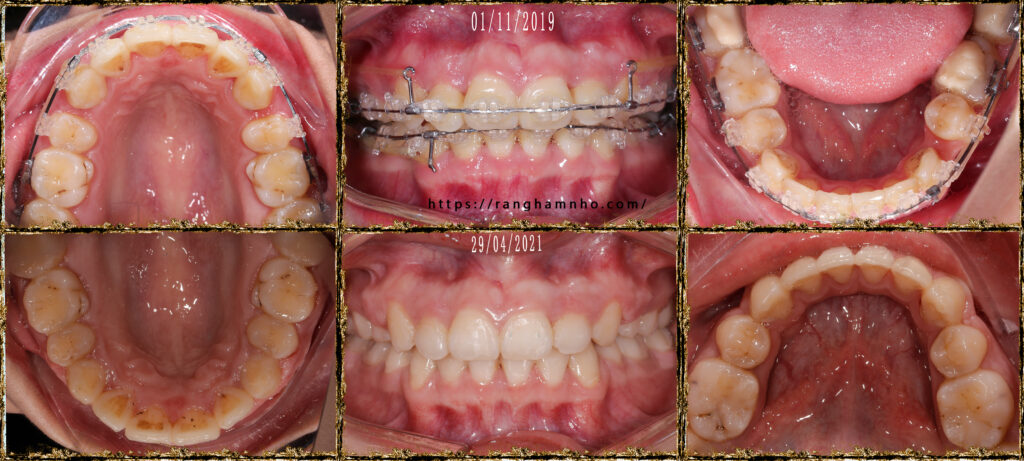

Trên ảnh chụp, vấn đề hiệu ứng cuôn xảy ra có vẻ không nặng như những case khác mà Dr. Răng Hàm Nhỏ tiếp nhận hỗ trợ kết thúc. Tuy nhiên, tiếp cận kết thúc case này cũng khá mất thời gian, do hiệu ứng cuộn làm mắc hàm trên thường xuyên cắn chạm mắc cài hàm dưới, đặc biệt là nhóm răng cửa và răng nanh hàm dưới. Hồ sơ chỉnh nha cho thấy BN thường xuyên bong mắc cài răng nanh dưới, cánh mắc cài răng nanh dưới có dấu hiệu gãy vỡ nhiều.

Xử lí tuần tự với cung tiện ích, reverse cure spee….. Đến giai đoạn cuối, đặt 2 minivis hàm trên để đánh lún thêm nhóm răng cửa trên nhằm cải thiện cười hở lợi của bệnh nhân.

Tháo niềng và đeo hàm duy trì tháo lắp Hawley